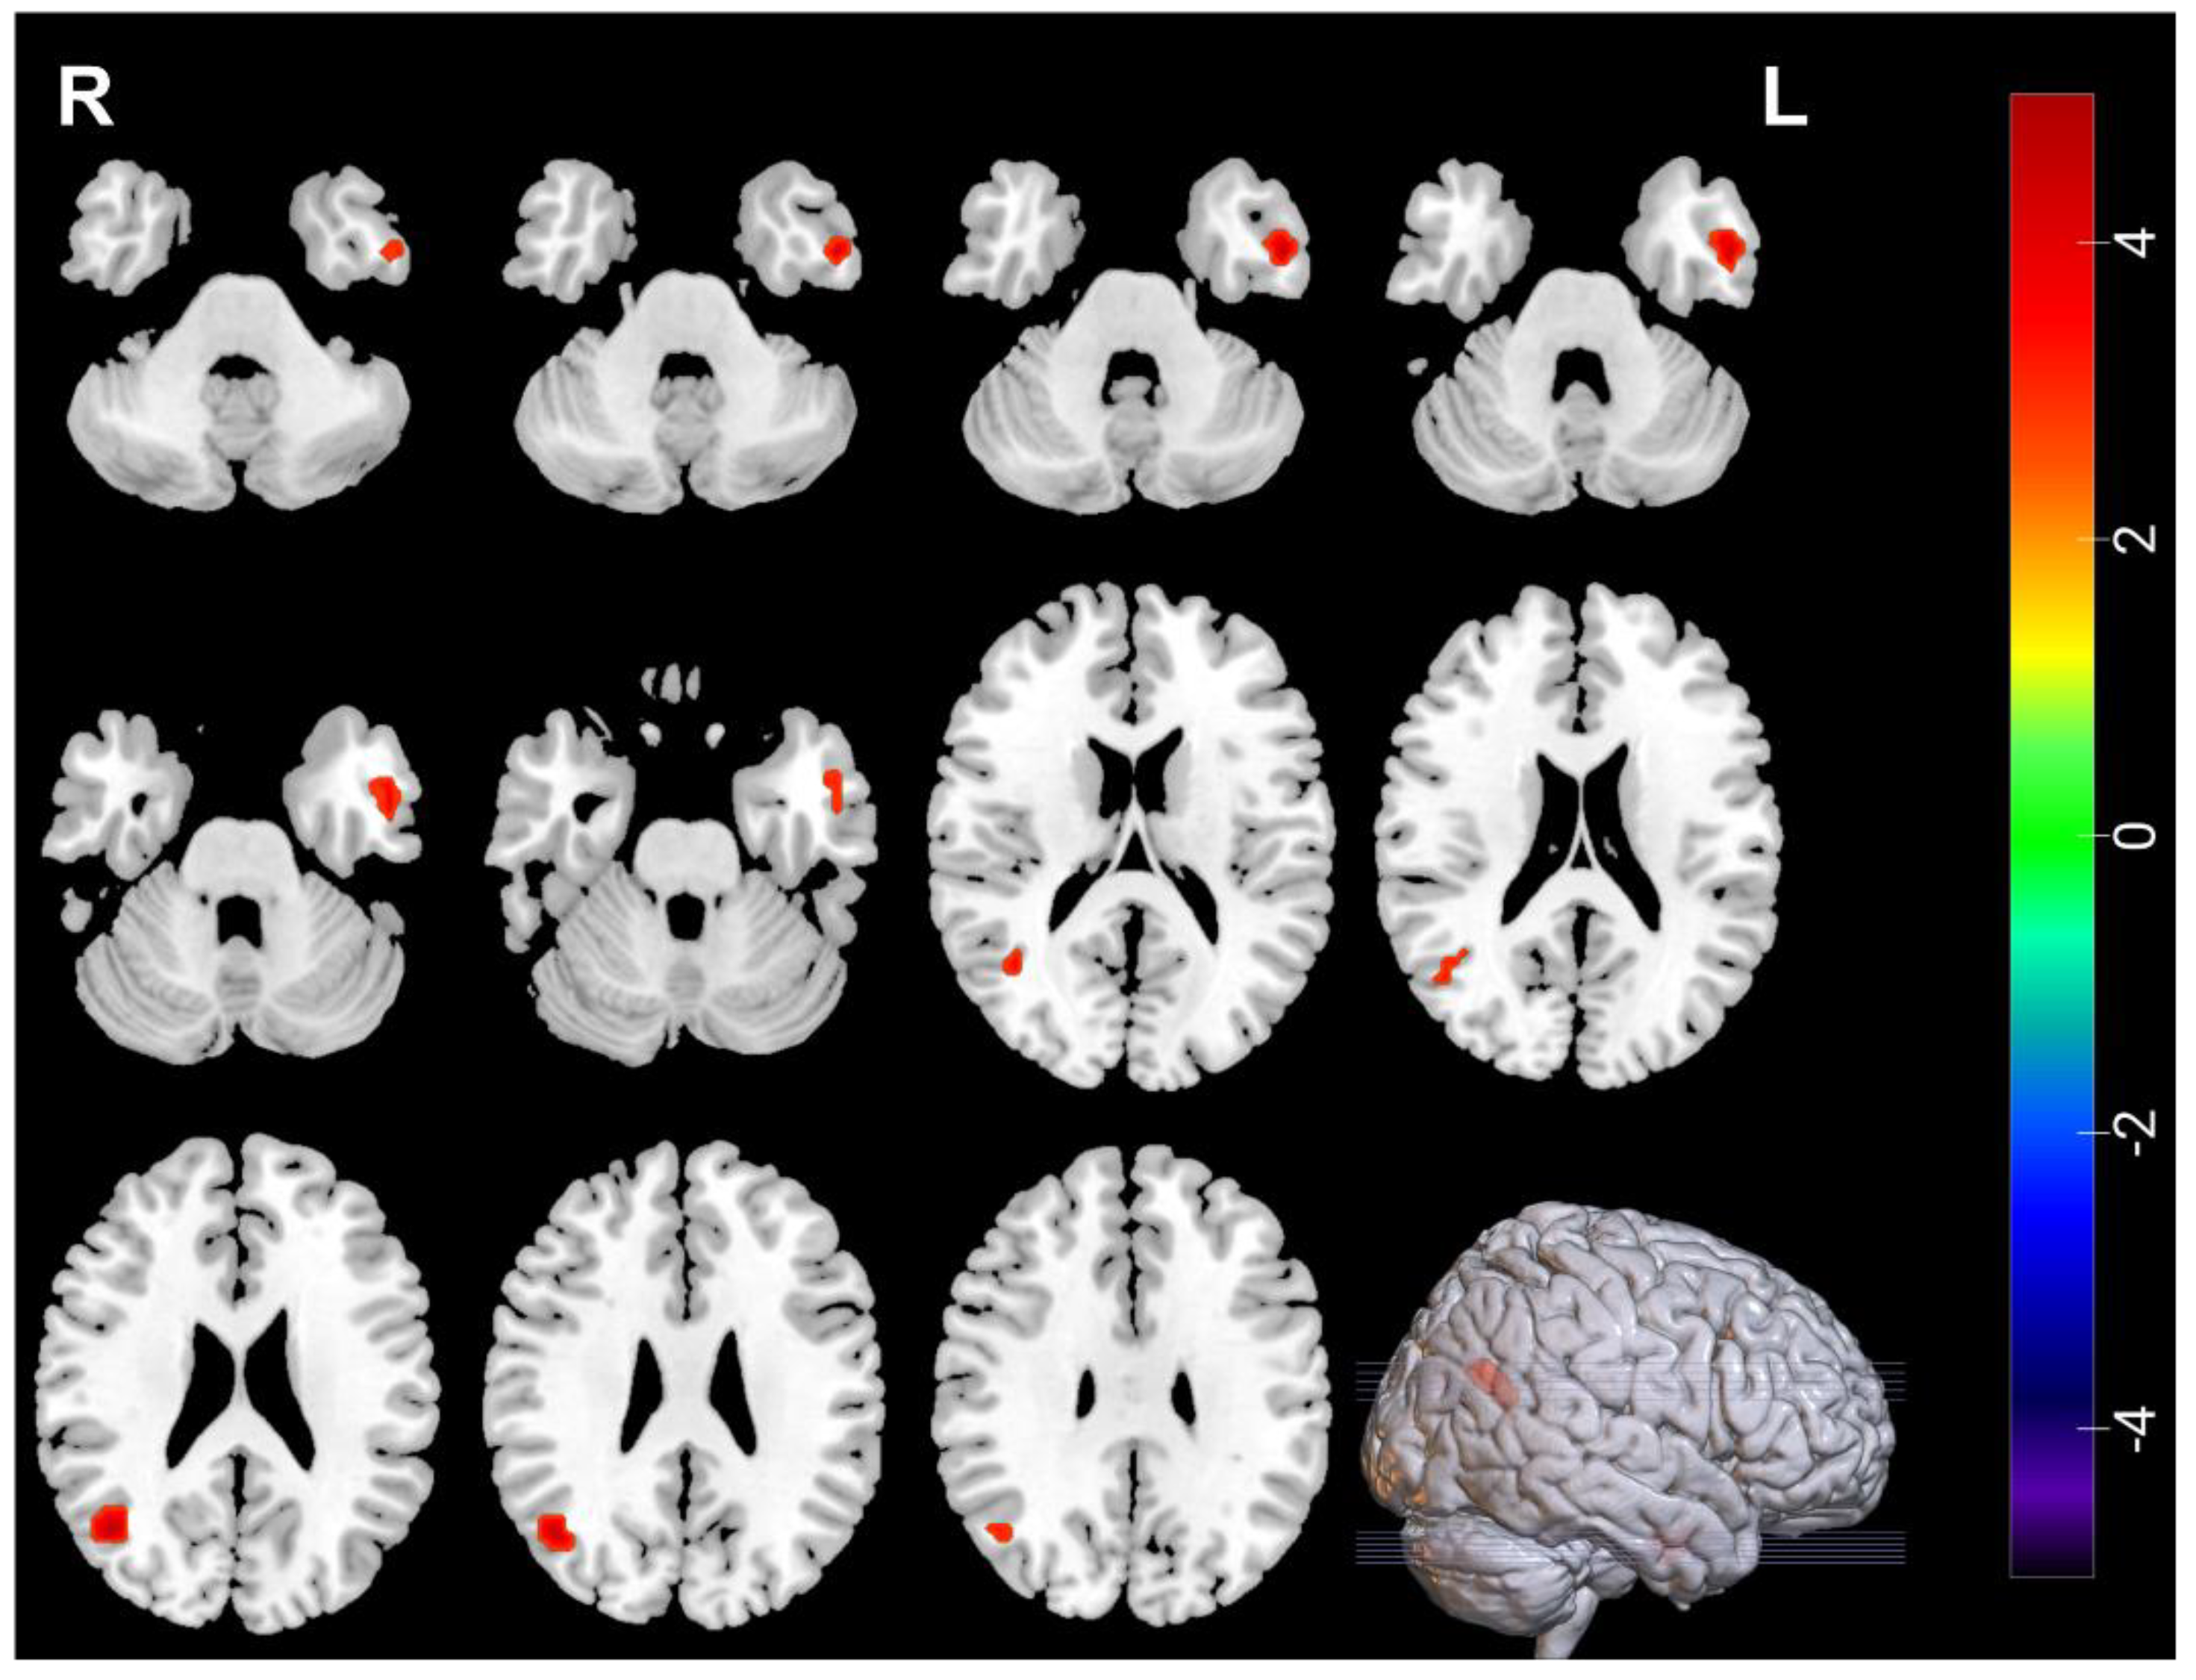

| Measures | Brain Regions | Voxel Size | Peak t Value | MNI Coordinates | ||

|---|---|---|---|---|---|---|

| Decreased | ||||||

| ALFF | Temporal_Pole_Sup_L | 30 | −4.0615 | −51 | 18 | −15 |

| ALFF | Frontal_Inf_Oper_L | 39 | −3.9169 | −54 | 12 | 12 |

| ALFF | Frontal_Mid_R | 34 | −4.2384 | 42 | −3 | 51 |

| Increased | ||||||

| ALFF | Occipital_Mid_R | 30 | 3.7765 | 42 | −66 | 24 |

| ReHo | Occipital_Mid_R | 46 | 4.5719 | 42 | −63 | 24 |

| ReHo | Temporal_Inf_L | 38 | 4.761 | −51 | −3 | −33 |